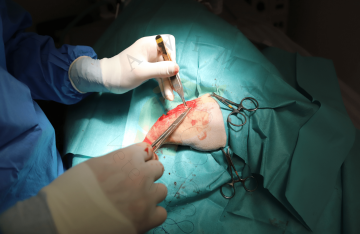

Trochleoplastika

Transpozice tuberositas tibiae

Náhrada předního zkříženého vazu

Amputace